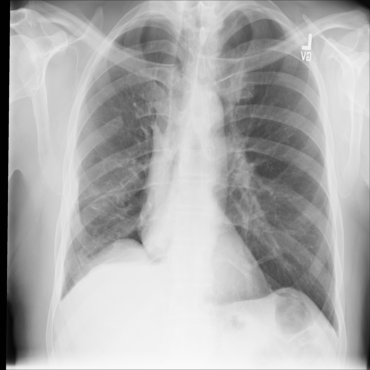

The availability of large public datasets and the increased amount of computing power have shifted the interest of the medical community to high-performance algorithms. However, little attention is paid to the quality of the data and their annotations. High performance on benchmark datasets may be reported without considering possible shortcuts or artifacts in the data, besides, models are not tested on subpopulation groups. With this work, we aim to raise awareness about shortcuts problems. We validate previous findings, and present a case study on chest X-rays using two publicly available datasets. We share annotations for a subset of pneumothorax images with drains. We conclude with general recommendations for medical image classification.